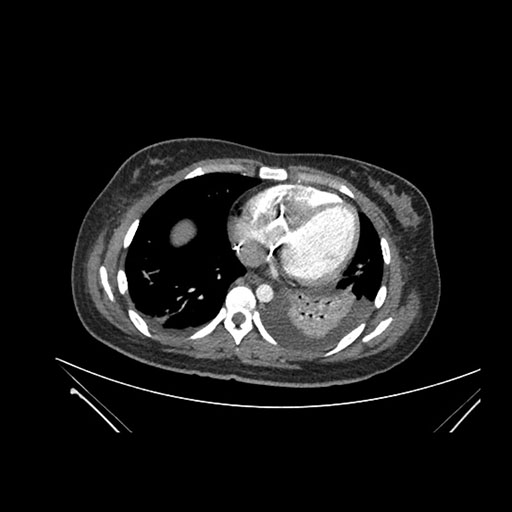

Axial Arterial

Axial Venous